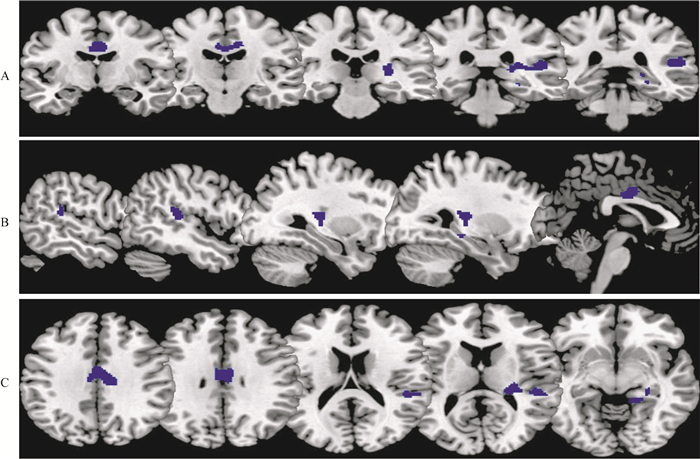

影像学与量表结果 与NPOCD组相比,POCD组术前MRI扣带回CBF显著降低(图 2);扣带回CBF与神经精神量表JLOT、BVMT-D、DST-B的Z分的相关系数(r值)分别为-0.631、-0.480、-0.533,差异具有统计学意义(P < 0.05)。

| Voxel-based comparison superimposed onto Montreal Neurologic Institute standard brain in the coronal (A), axial (B), and sagittal planes (C). 图 2 POCD组与NPOCD组术前扣带回脑血流差异 Fig 2 Differences in preoperative CBF in cingulate between POCD and NPOCD patients |